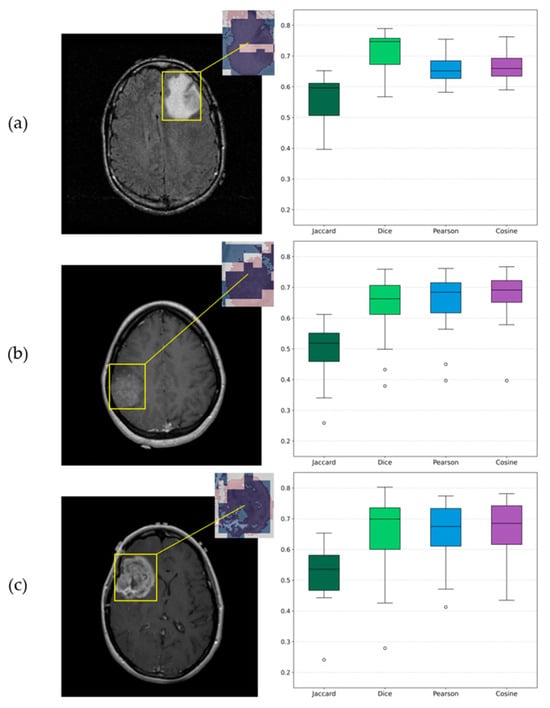

| Sample | Jaccard | Dice | Pearson | Cosine |

|---|---|---|---|---|

| Grade 2 | 0.56 ± 0.08 [0.51–0.61] | 0.72 ± 0.07 [0.68–0.76] | 0.66 ± 0.05 [0.63–0.69] | 0.67 ± 0.05 [0.64–0.70] |

| Grade 3 | 0.50 ± 0.10 [0.44–0.56] | 0.63 ± 0.11 [0.56–0.70] | 0.64 ± 0.11 [0.57–0.71] | 0.65 ± 0.12 [0.57–0.73] |

| Grade 4 | 0.51 ± 0.10 [0.45–0.57] | 0.64 ± 0.14 [0.55–0.73] | 0.65 ± 0.10 [0.59–0.71] | 0.66 ± 0.11 [0.59–0.73] |

3.5. Explainable AI Insights